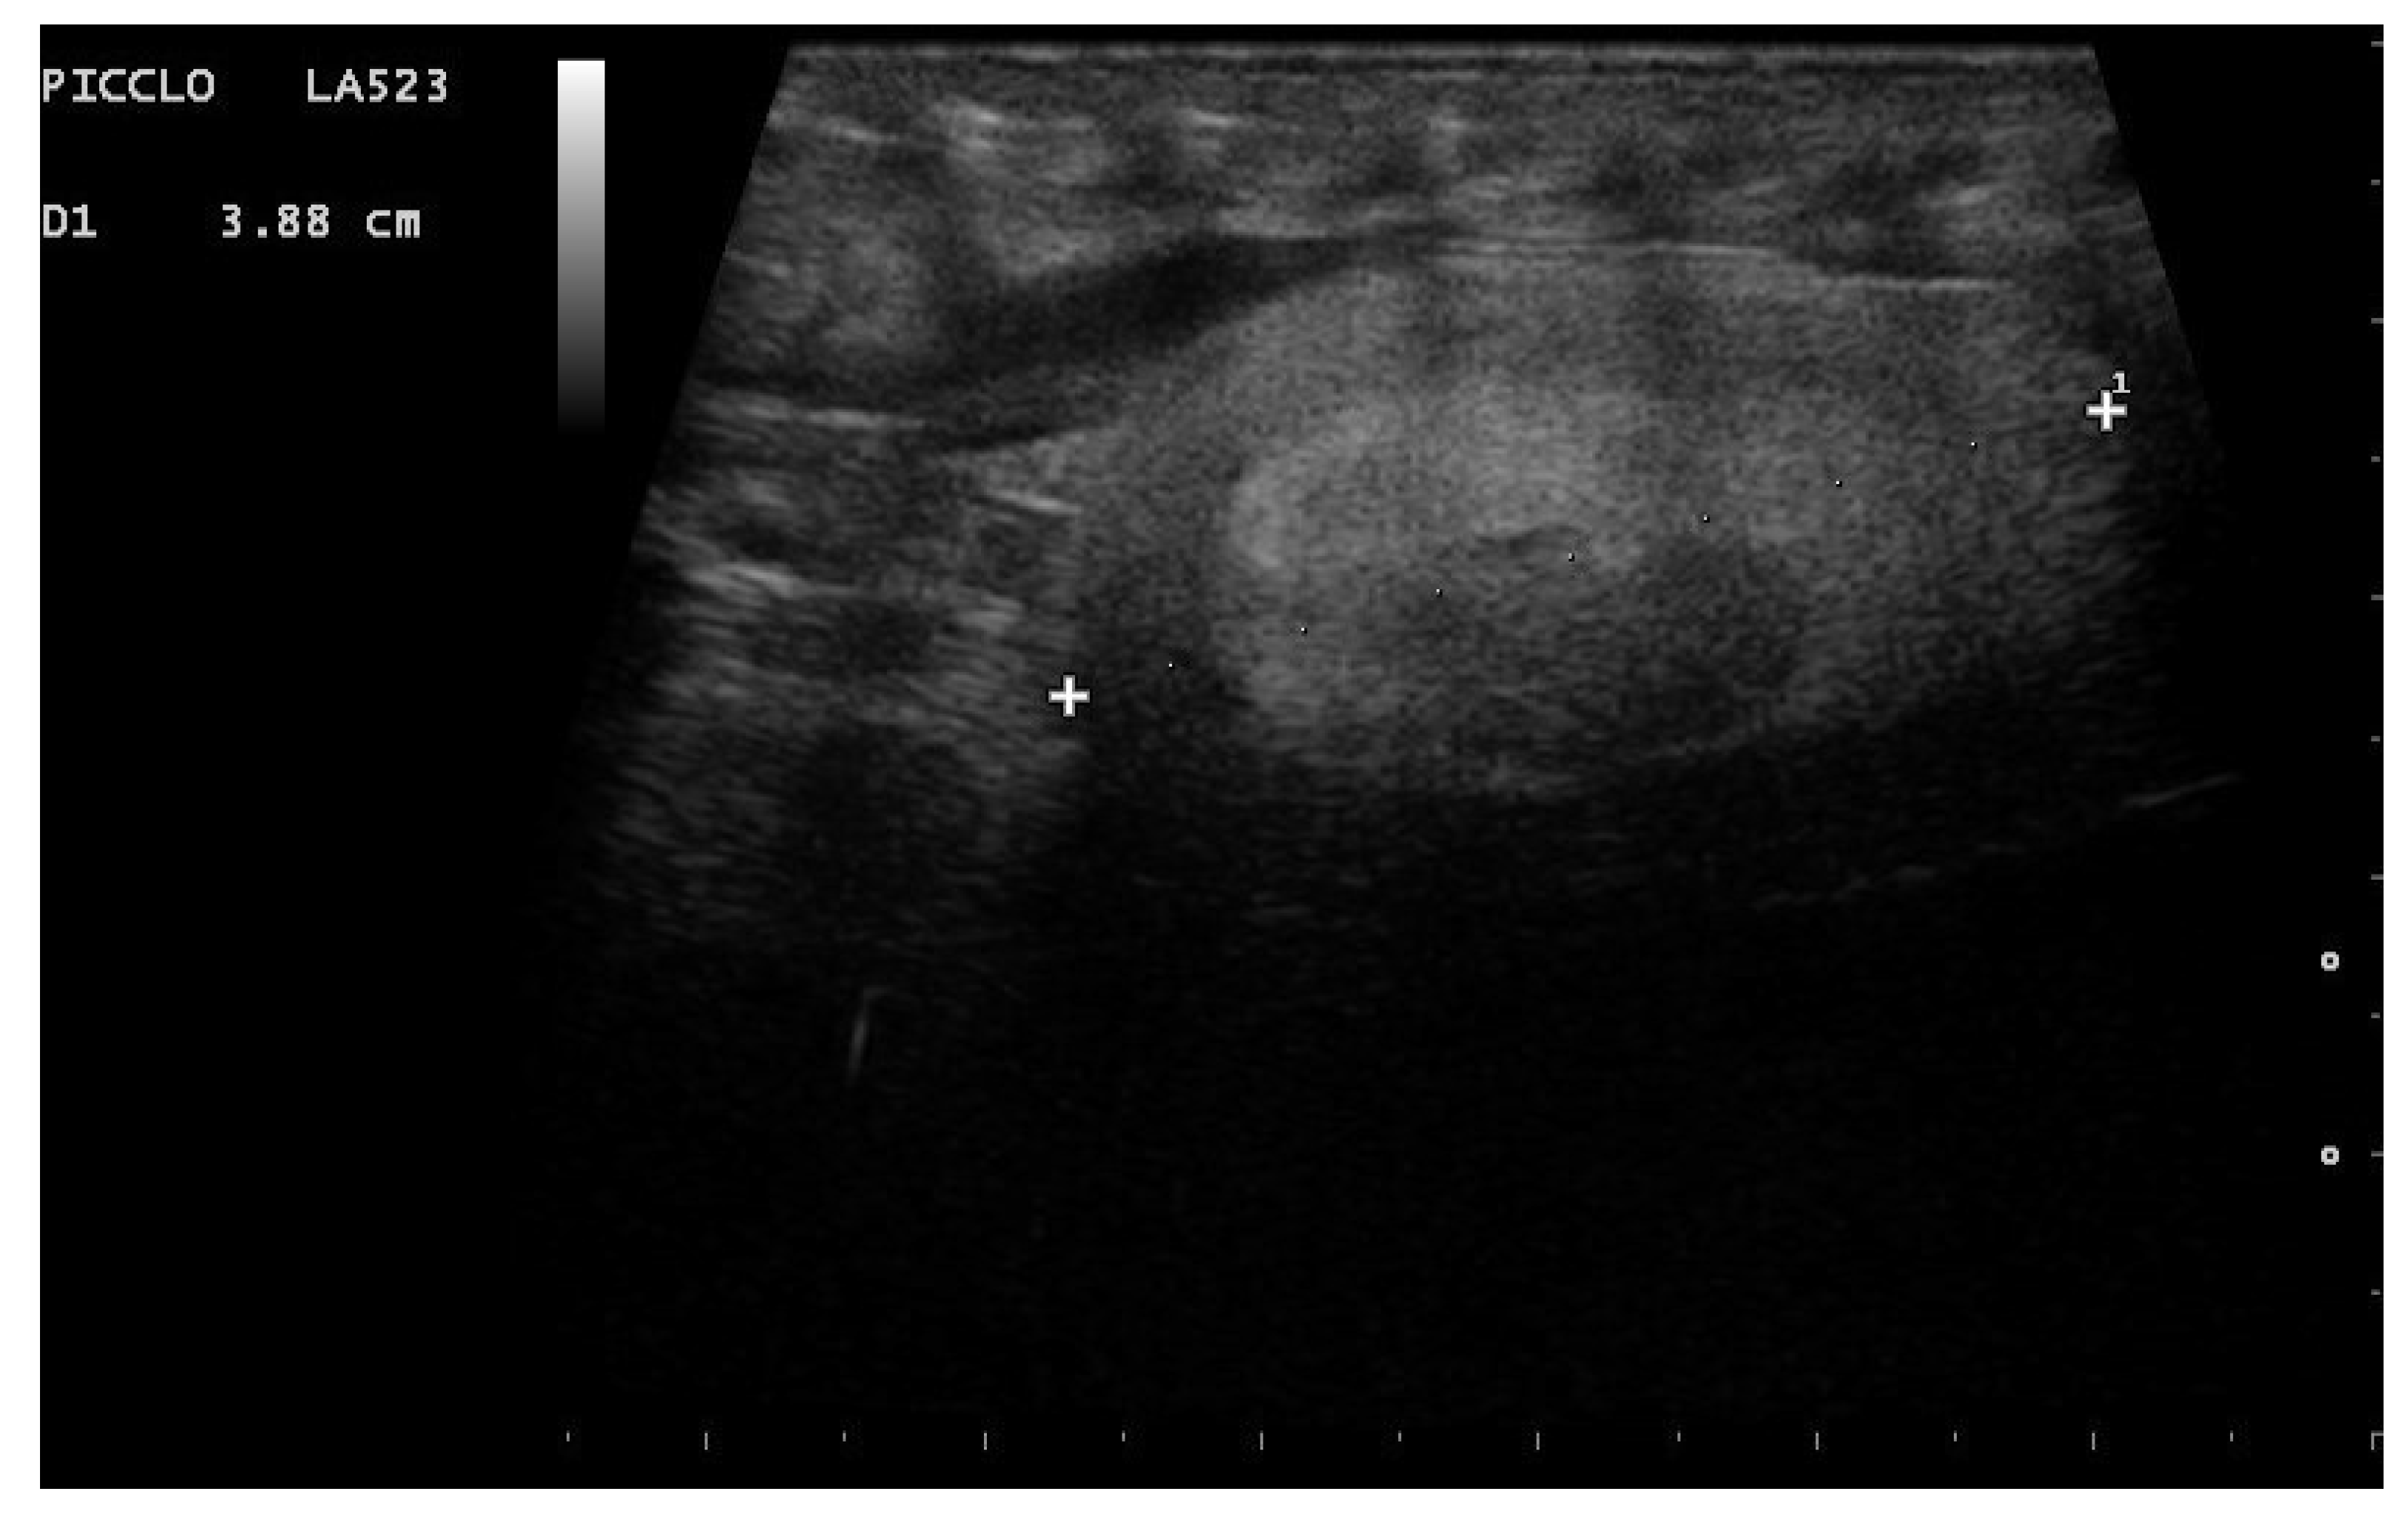

- Garcia, V.C.; Almeida-Santos, S.M. Reproductive cycles of neotropical boid snakes evaluated by ultrasound. Zoo Biol. 2021, 1–10. [Google Scholar] [CrossRef]

- Isaza, R.; Ackerman, N.; Jacobson, E.R. Ultrasound imaging of the coelomic structures in the Boa constrictor (Boa constrictor). Vet. Radiol. Ultrasound 1993, 34, 445–450. [Google Scholar] [CrossRef]